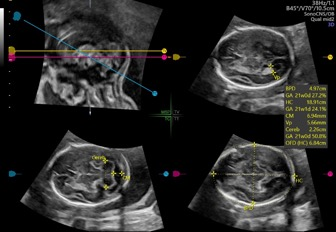

SonoCNS

自动识别4个标准切面:

正中矢状面,经丘脑平面,经小脑平面,经侧脑室平面

自动测量6组生物指标:

BPD 双顶径,HC 头围,CM 后颅窝池,Cereb. 小脑横径,Vp 侧脑室后脚,OFD 枕额径